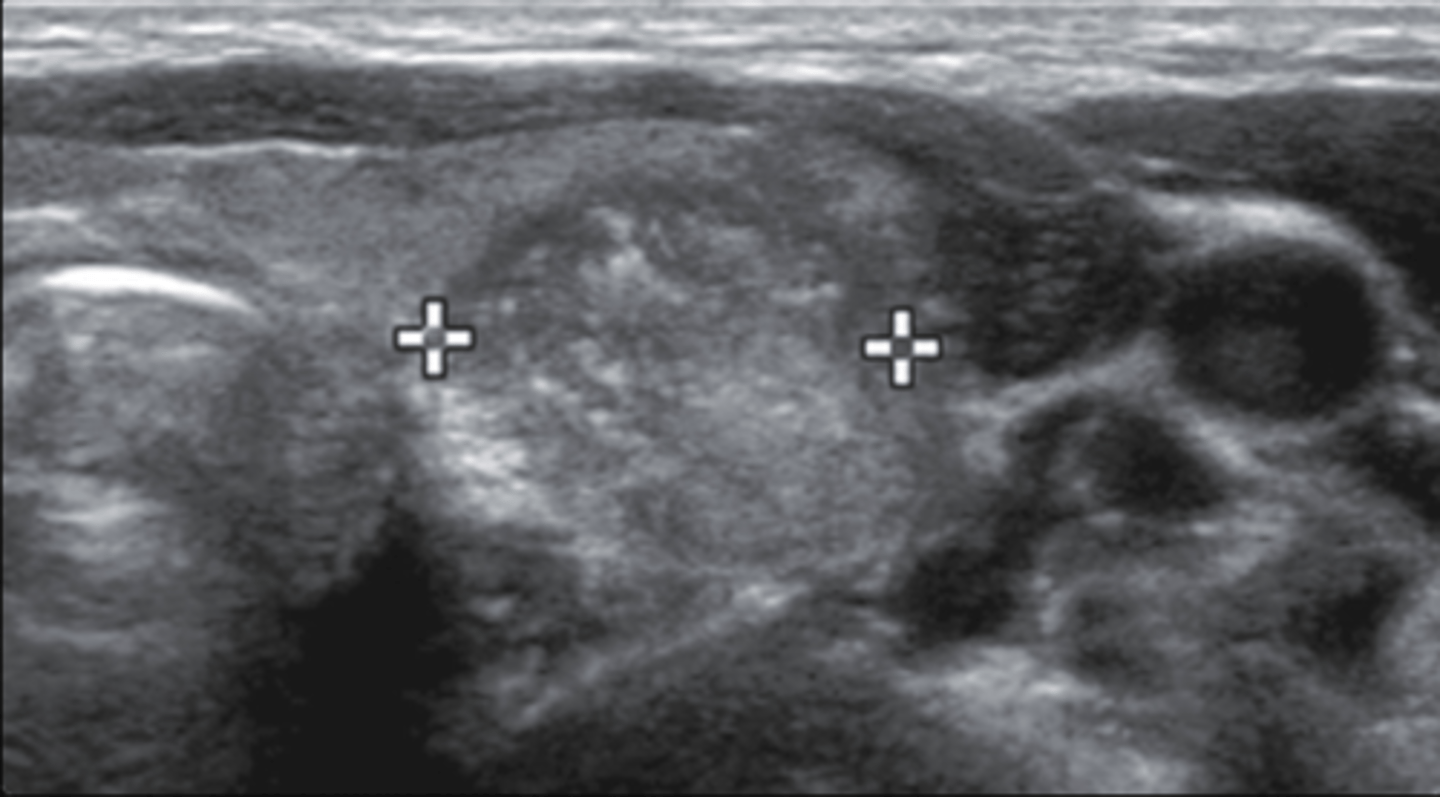

12. The structure that is measure in Figure 12-27 was discovered in an asymptomatic patient. Which of the following sonographic features is present and consequently most worrisome for malignancy?

a. Anechoic echogenicity

b. Internal microcalcifications

c. Eggshell calcifications

d. Colloid artifact